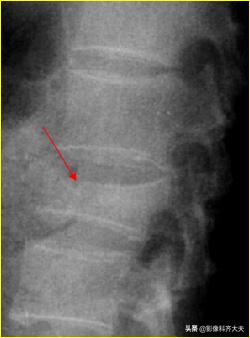

椎体压缩骨折:

病史:高处坠落;重物冲击

X线表现:椎体楔形变,前缘凹陷;前后左右径增大,间隙正常;椎体中部密度增高,小梁紊乱;椎体、椎弓常见骨折碎片;脊椎后突、成角、移位。

胸12及腰2楔状变形,胸12椎体前缘可见碎骨片